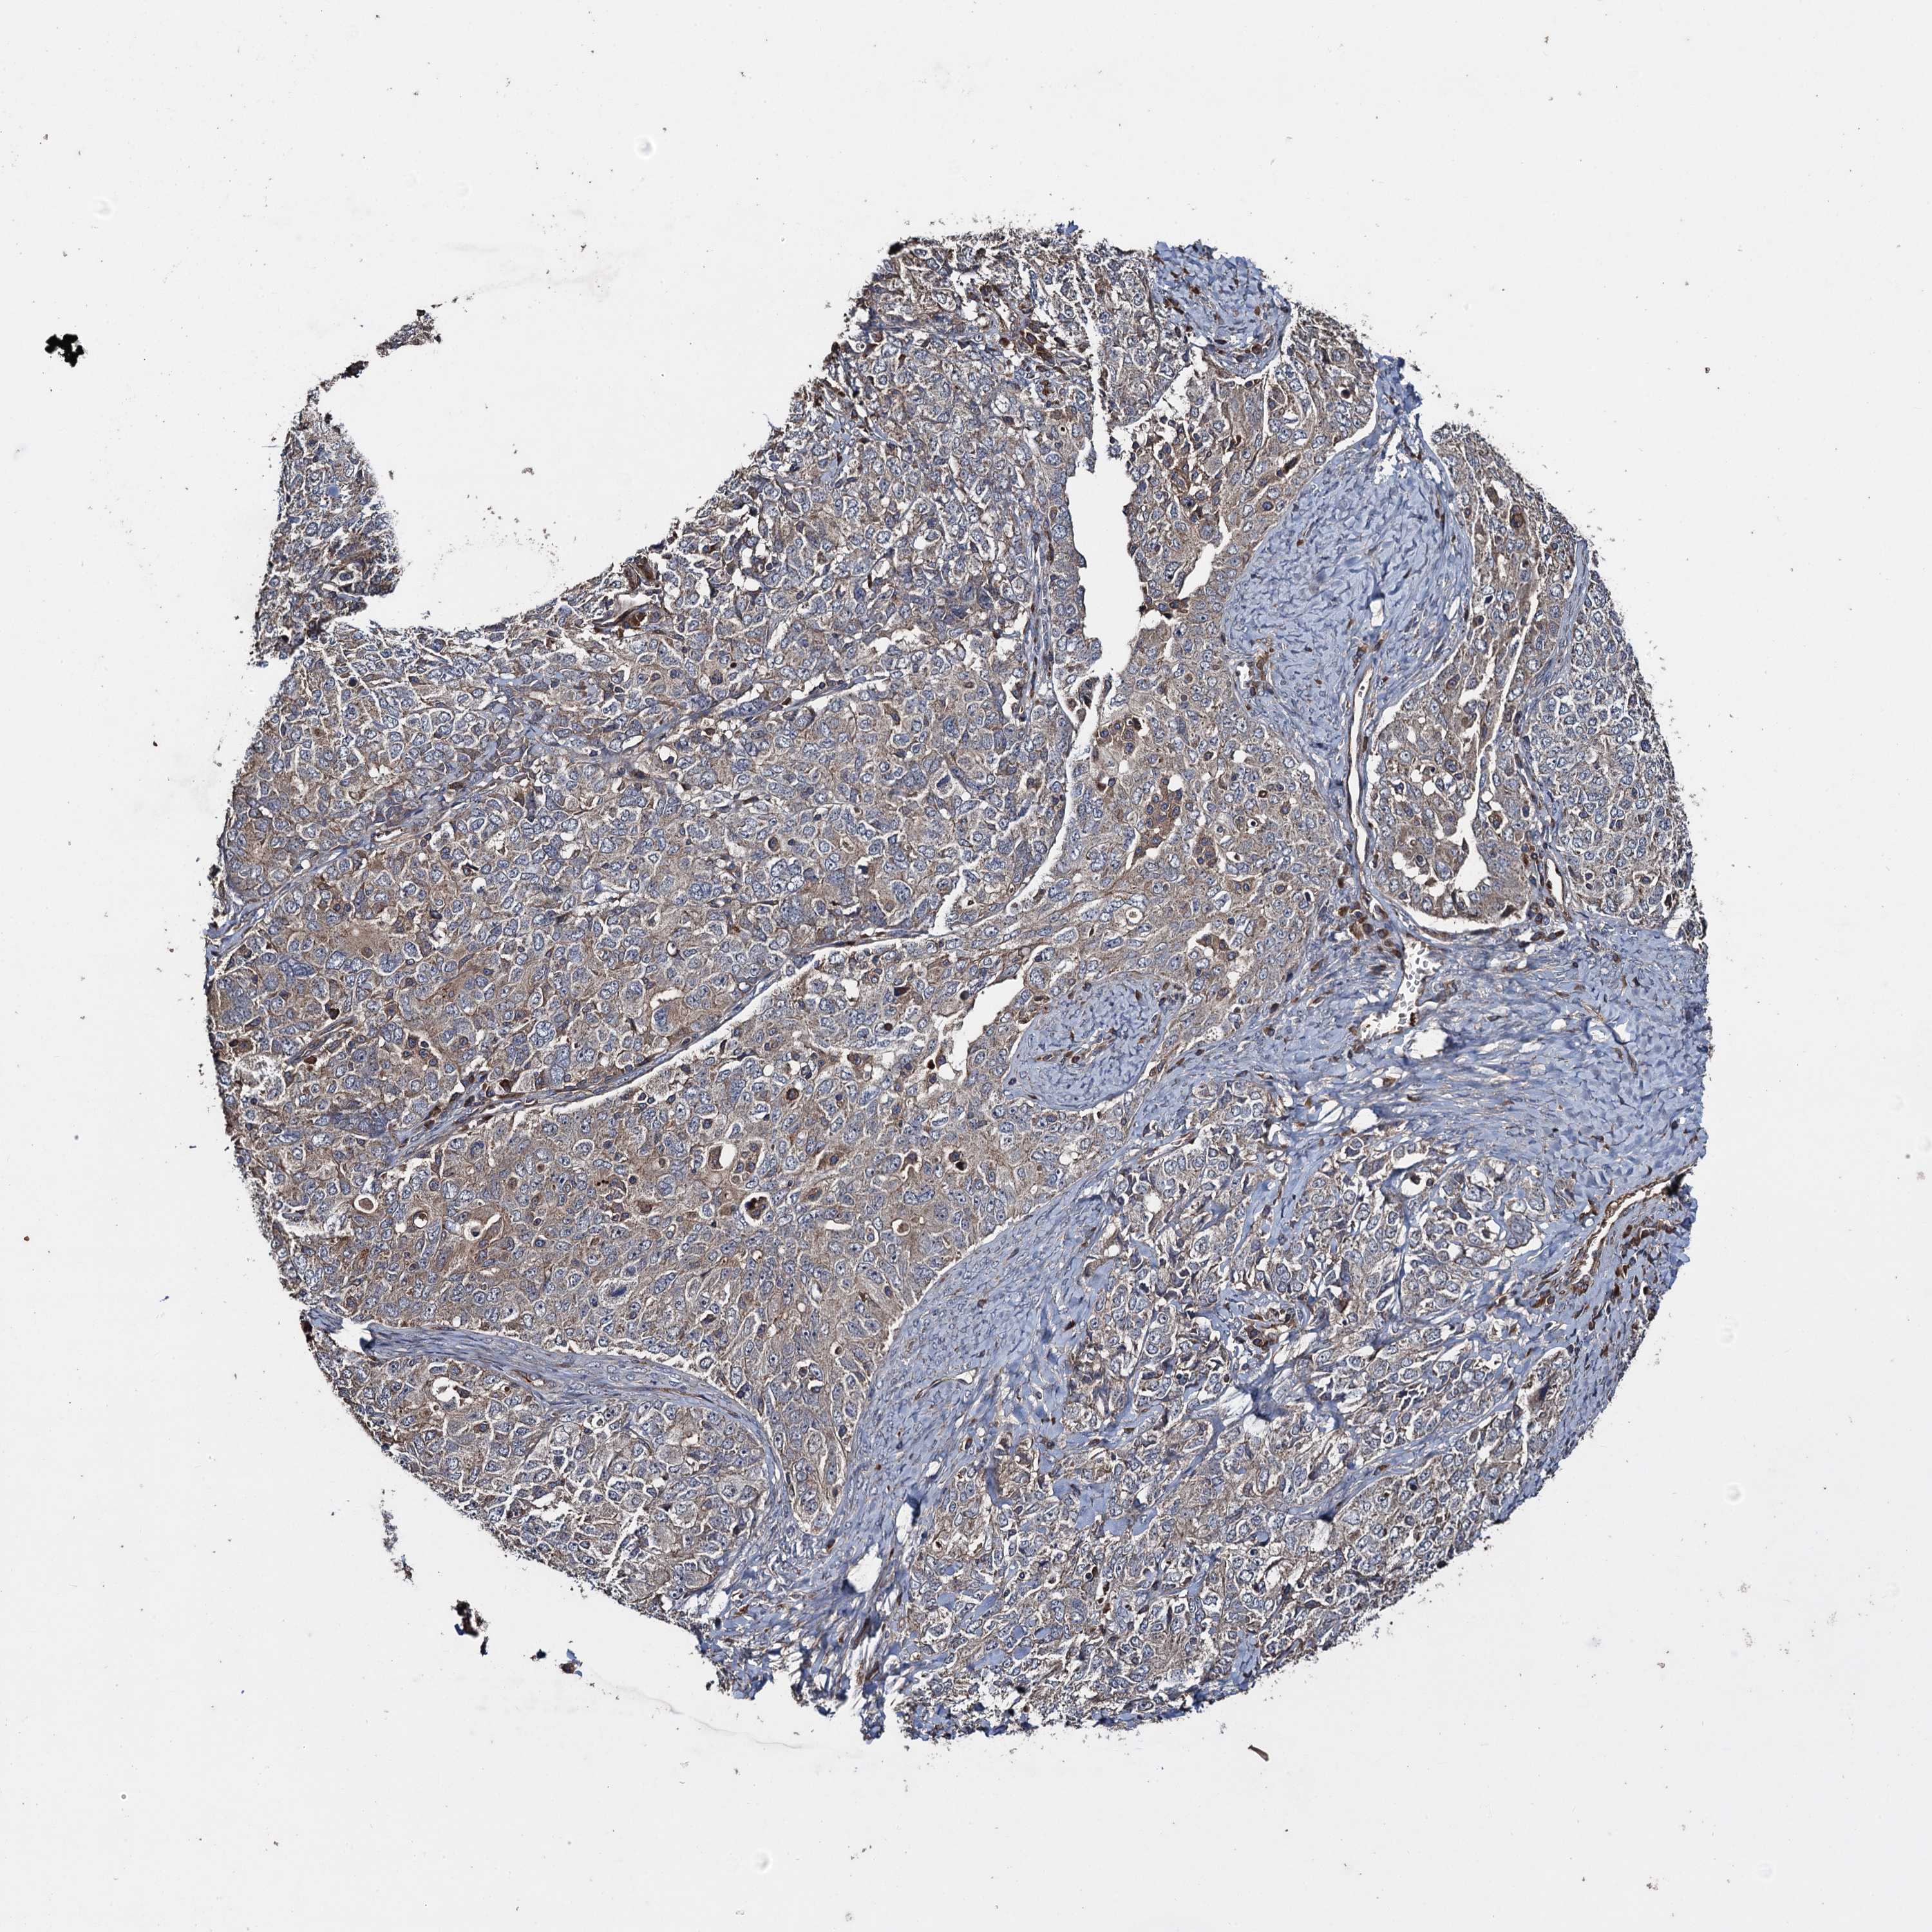

OVARIAN CANCER - Protein expressioni

A mouse-over function shows sample information and annotation data. Click on an image to view it in a full screen mode. Samples can be filtered based on level of antibody staining by selecting one or several of the following categories: high, medium, low and not detected. The assay and annotation is described here.

Note that samples used for immunohistochemistry by the Human Protein Atlas do not correspond to samples in the TCGA dataset.

Antibody stainingi

Antibody staining in the annotated cell types in the current human tissue is reported as not detected, low, medium, or high, based on conventional immunohistochemistry profiling in selected tissues. This score is based on the combination of the staining intensity and fraction of stained cells.

Each image is clickable and will lead to virtual microscopy that enables deeper exploration of all samples and also displays staining intensity scores, fraction scores and subcellular localization as well as patient and tissue information for each sample.

Antibody HPA041174

Antibody HPA041390

Cystadenocarcinoma, serous, NOS